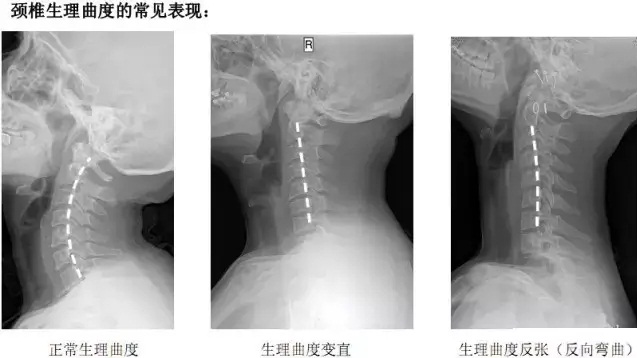

其实,人体颈椎有一个生理曲度,各个椎体后缘形成一个连续光滑的曲线。但是,有的人因为长时间不正确的坐姿,长时间的劳累,颈椎缺少活动、脊柱损伤生理曲度,就会导致颈部生理弯曲变直,严重的甚至反曲,生理曲度就被破坏了。枕啤酒瓶治颈椎在某种程度上好似是契合生理曲度,对颈椎有一定的帮助,但因为啤酒瓶置于颈椎下方, 并不完全符合生理曲度可能会对颈椎造成伤害,且脊椎病复杂,所以并不建议用此方法治疗颈椎病。

其次,枕头不能太低。人体的颈部具有着正常的生理弧度,即颈脊柱轻度前凸。这种生理曲线不但保证了颈椎外在肌群的平衡,而且对保持椎管内的生理解剖状态具有重要作用。枕头同样不符合因生理生理曲度,使得颈椎张力过大而疲劳,形成慢性损伤,甚至造成黄韧带屈曲向前突入椎管诱发颈椎病。